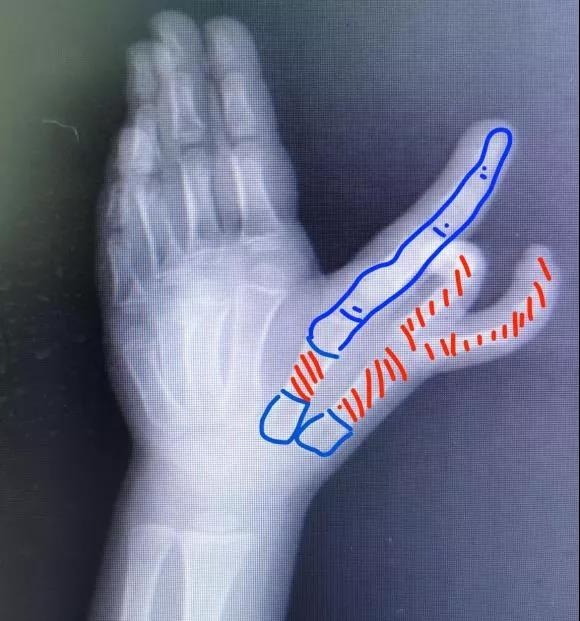

图为术前手术切口的设计

图为术前截骨水平设计,红色为切除骨质